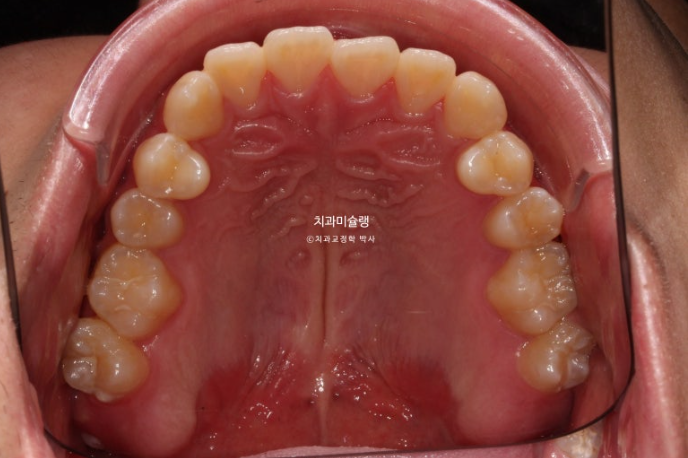

중심선이 어긋나있고 앞니 개방교합이 보입니다.

주걱턱으로 인해 앞니가 거꾸로 물리는 반대교합이 있습니다.

어금니 교합관계도 심한 3급입니다.

치료계획은 아래 사랑니 2개를 발치하고 사랑니 공간으로 치열을 뒤로 미는 것 입니다.

클리피씨 선택 하고 치료에 들어갔습니다.